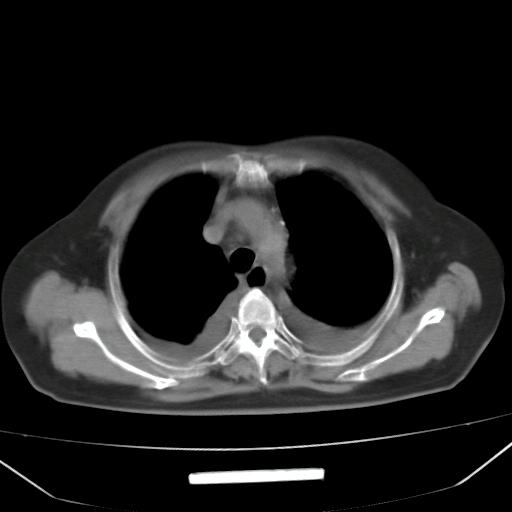

以下是引用liuyue在2008-4-19 22:25:00的发言:[br]先考虑:1.心衰伴肺水肿、双侧胸腔积液、叶间积液、双下肺不完全性肺不张; [br] 2.冠状动脉粥样硬化。

以下是引用lijuanln在2008-4-19 23:05:00的发言:[br]两侧胸腔积液,肺水肿[br]心包积液[br]提示心衰

以下是引用jiangjing在2008-4-20 10:43:00的发言:[br]结合病史支持 冠心病[冠状动脉钙化],心功能不全,肺淤血、肺水肿,双侧胸腔与斜裂积液